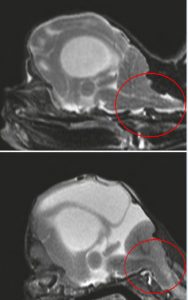

Lo studio ha esaminato 45 persiani dalla faccia piatta e 47 dalla faccia estremamente piatta e ha scoperto che le mascelle di quelli con brachicefalia estrema erano chiaramente disallineate, i gatti non avevano una parte visibile del cranio a cui attaccare i muscoli della mascella, alcuni avevano una mascella che sporgeva nella sua parte inferiore e alcuni hanno anche mostrato anomalie dei denti, che possono portare a difficoltà alimentari. Altre deformità includevano “difetti ossei”: i fori nel cranio che puoi vedere nella figura sotto. Questi erano più pronunciati nei teschi dei gattini che puoi vedere nelle due immagini in basso a destra. Anomalie nelle ossa della cavità nasale hanno portato a un certo blocco dei passaggi nasali, che comporterebbe difficoltà respiratorie.

I persiani dal muso estremamente piatto avevano anche teschi anormalmente a forma di cupola (vedi figura sopra). Lo spazio all’interno della scatola cranica è stato ridotto, portando alla compressione del cervello. Un terzo di questi persiani aveva chiari segni di idrocefalo interno, un accumulo di liquido all’interno del cervello. Questo è associato a molti problemi nei gatti, comprese convulsioni e cecità. Nella maggior parte dei persiani col muso molto schiacciato, la parte posteriore del cervello sporgeva anche dalla base del cranio e nel midollo spinale (questo è stato visto anche in alcuni dei persiani con il muso meno schiacciato).

In cinque gattini con muso molto piatto, la compressione cerebrale era così grave che la parte posteriore del cervello era stata spinta fuori dal cranio nello spazio nella colonna vertebrale dove si trova il midollo spinale (vedi figura qui sotto). Questi gattini non erano in grado di stare in piedi o camminare correttamente, non erano vigili, avevano tremori alla testa, movimenti oculari incontrollati e occhi disallineati, schemi respiratori anormali, ei loro proprietari hanno riferito frequenti miagolii senza alcuno scopo e di lunga durata. I gattini sono stati soppressi perché troppo sofferenti. La sofferenza nella breve vita di questi gattini, a causa del desiderio di un certo aspetto, è del tutto inaccettabile.